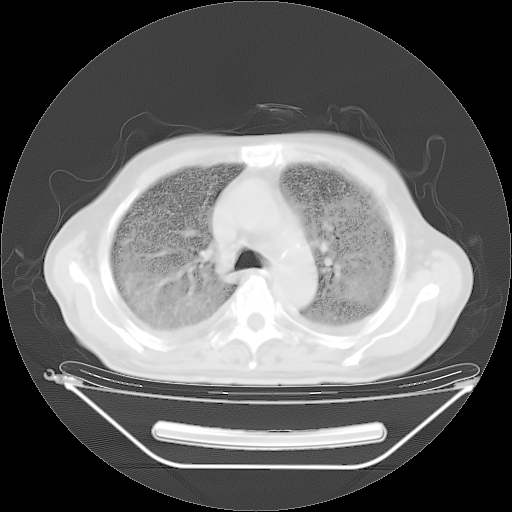

胸腹部CT,诊断意见:左上肺叶钙化灶、左侧胸膜局限性增厚并钙化、胆囊炎。描述部分肺组织呈磨玻璃样改变。